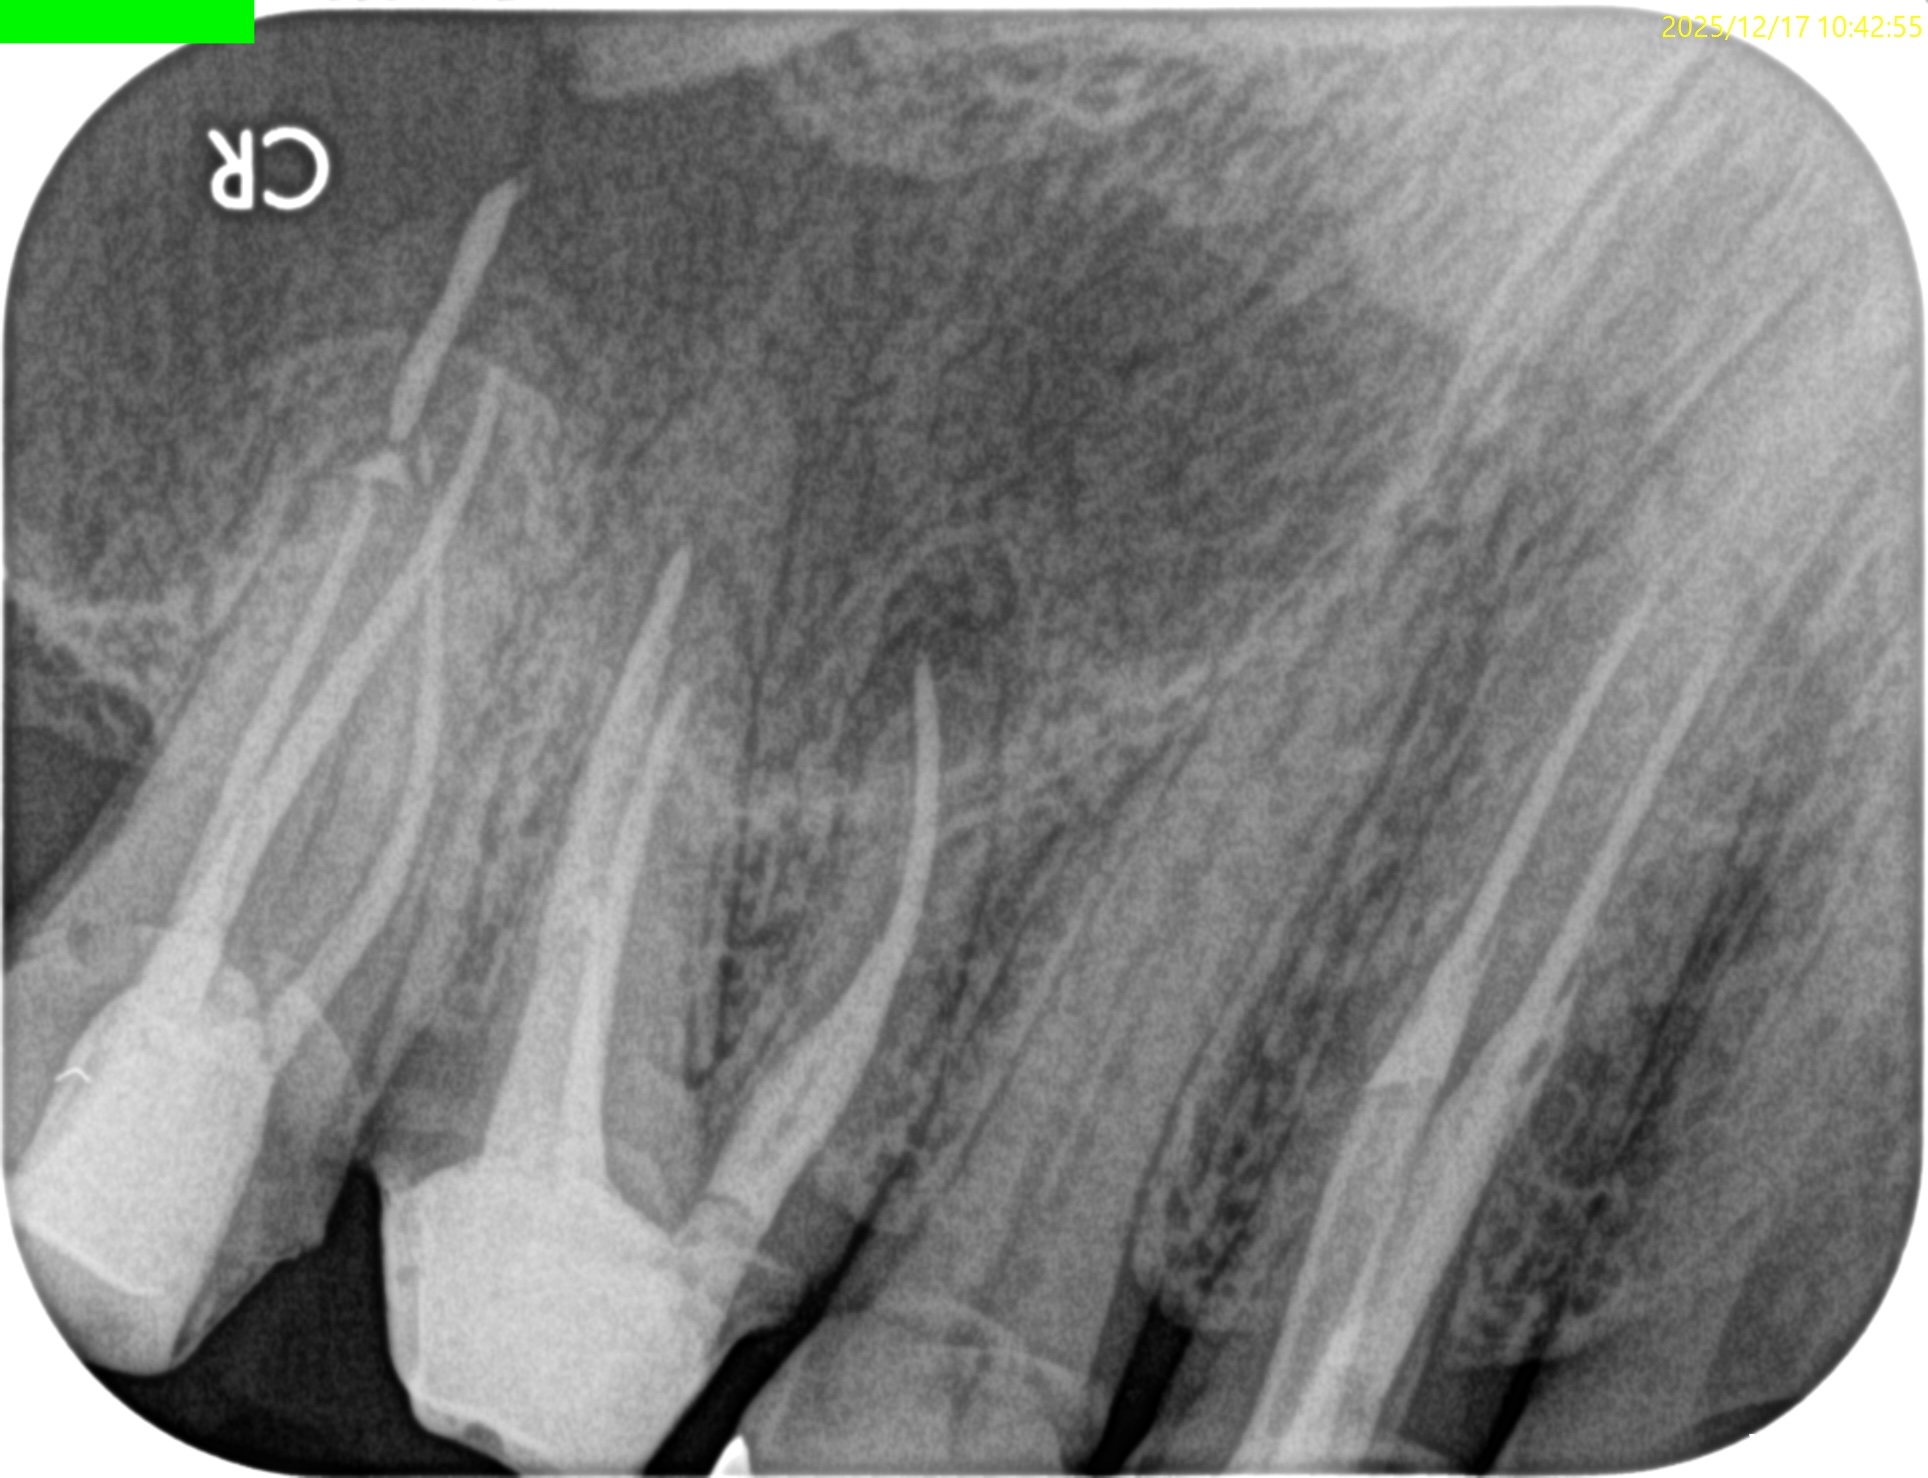

紹介患者さんの治療で、#3 MB Apicoectomyを行ったのだが

MBをRoot resectionした。

ここまでは容易なのだが、この後に逆根管形成・逆根管充填を行うが、

明後日の方向に逆根管形成・逆根管充填してしまう

この状態ではMB2の封鎖がままならない。

さらに切断部位から4mm, 頬舌的幅径が6.7mm必要だが再切断し逆根管形成・充填を試みることにした。

再切断したら…

Apico-marginal deffectを人為的に作成してしまった。